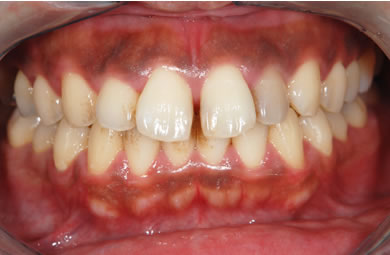

| 性別/年齢 | 男性 / 29歳 | ||||||||||||||||||||||||||||||||

| 主訴 | 歯並びを綺麗にしたい。奥歯の銀歯が目立つので白くしたい。 | ||||||||||||||||||||||||||||||||

| 治療方針 | 上の前歯部に関しては審美的回復の優先を切望されているため、透明感のあるオールセラミックのハイクオリティタイプを使用。 | ||||||||||||||||||||||||||||||||

| 治療内容 | オールセラミック(ハイクオリティ)3本、ハイブリッドセラミックインレー10本 | ||||||||||||||||||||||||||||||||

| 総治療費 | 714,286円 | ||||||||||||||||||||||||||||||||

| 治療期間 | 7ヶ月 |